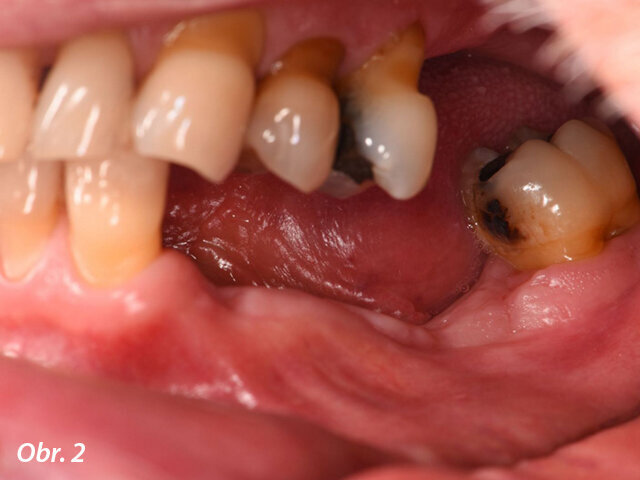

O osm týdnů později zjistilo klinické vyšetření omezené množství keratinizovaných tkání ve vestibulární oblasti zubu 34 a nepravidelný tvar bezzubého hřebene (obr. 2, 3).